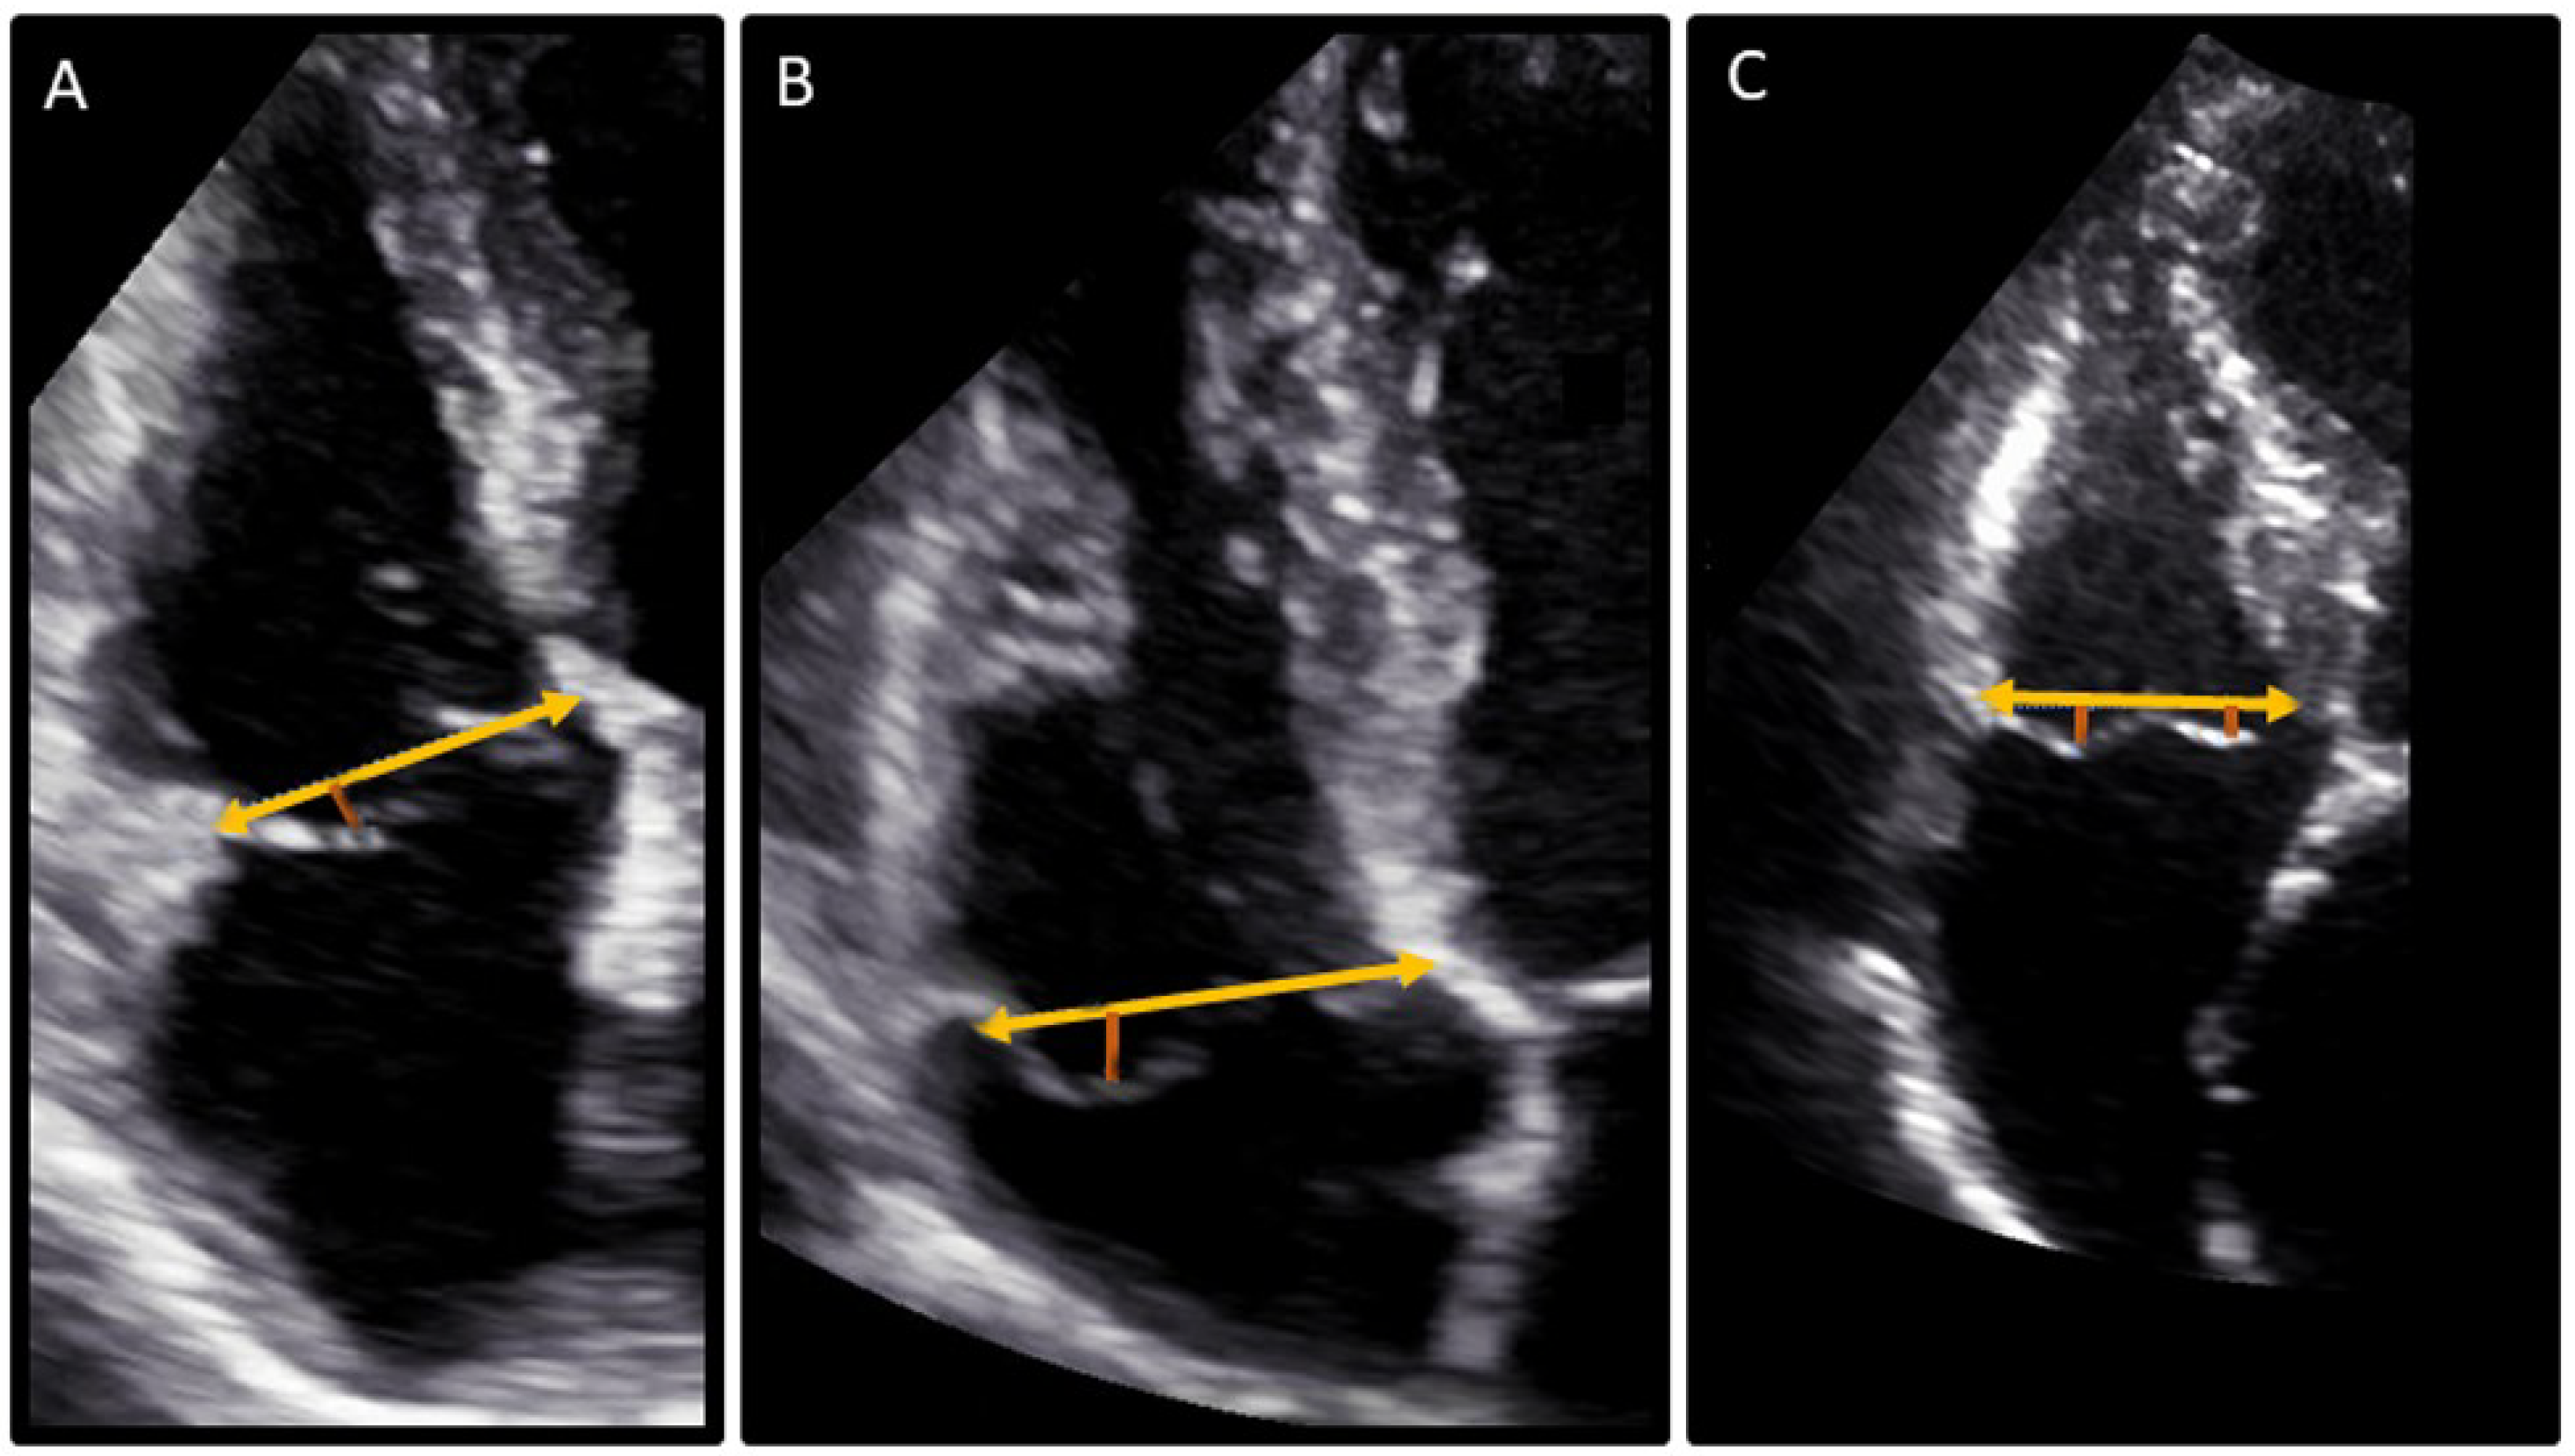

2.4. Definition of TV Prolapse

| Tricuspid annular disjunction *, n (%) | 11 (1) | 11 (12) | 0 (0) | <0.001 |